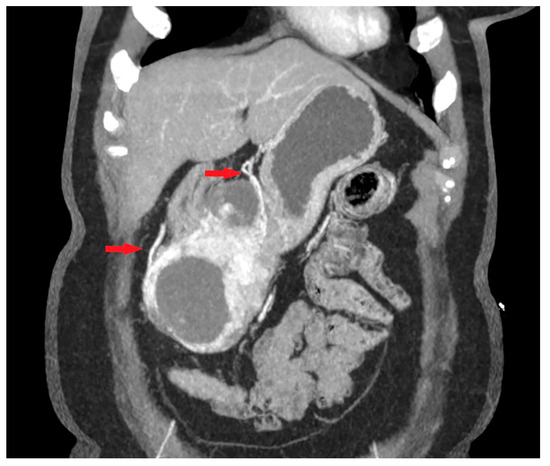

- Maximum diameter: the largest diameter of the tumor in mm (Figure 1);

- Tumor shape: regular or irregular (Figure 1);

- Growth mode: exophytic/mixed and endophytic (Figure 1);